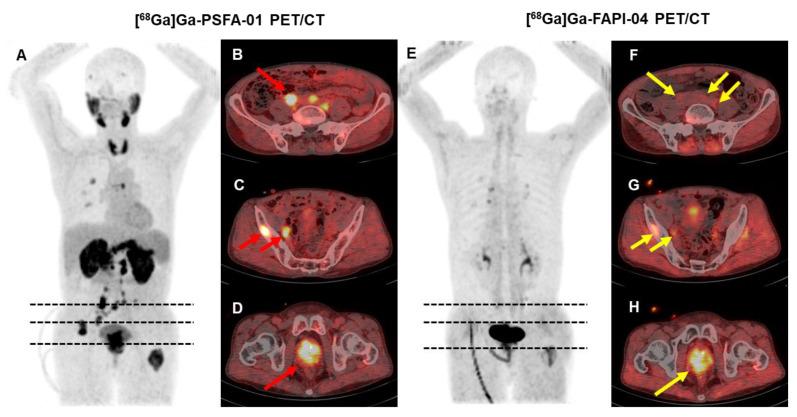

To assess the effectiveness of [Ga]Ga-PSFA-01 PET/CT in detecting primary tumors and metastatic lesions in patients with prostate cancer (PCa), and to compare the results with those from [Ga]Ga-PSMA-11 PET/CT and [Ga]Ga-FAPI-04 scans. Patients with histologically proven PCa were prospectively recruited and underwent [Ga]Ga-PSFA-01 PET/CT, of which: 25 participants also underwent [Ga]Ga-PSMA-11 PET/CT scan, 5 patients also underwent [Ga]Ga-FAPI-04 PET/CT scan, 3 patients underwent three modalities imaging. To assess the expression of PSMA and FAP, we obtained a pathological tissue section from a patient and performed immunohistochemical staining analysis. SUV, SUV, SUV and the number of detected lesions were compared by using the Wilcoxon signed-rank test, and the Mc-Nemar test was used to compare detectivity. Correlation between SUV and prostate cancer related clinical indicators was demonstrated with Spearman's ratio. A visual assessment was made to compare the detectability of primary tumors and metastases in different regions. A total of 33 patients with a median age of 70 years (range: 52-89 years) were enrolled. Including 13 patients for initial staging and 20 for recurrence detection. [Ga]Ga-PSFA-01 demonstrated superior performance in both patient-based and lesion-based analyses than [Ga]Ga-PSMA-11 PET/CT. However, [Ga]Ga-PSFA-01 depicted lower uptake in primary tumors (11.13 ± 7.04 vs. 15.44 ± 9.25, p = 0.009), bone metastases (8.50 ± 5.0 vs. 12.43 ± 9.55, p < 0.001) and metastases in other sites (6.05 ± 3.29 vs. 10.73 ± 8.74, p = 0.028) , lower tumor to background ratio (TBR) than [Ga]Ga-PSMA-11 PET/CT (2.86 ± 1.50 vs. 9.50 ± 5.62, p < 0.001). [Ga]Ga-PSFA-01 PET/CT showed more lesions (24 vs. 13, p = 0.18), higher uptake (primary tumors, 10.27 ± 2.42 vs. 7.32 ± 0.17, p = 0.109; bone metastases, 8.14 ± 5.98 vs.4.52 ± 1.22, p = 0.128; pelvic lymph nodes, 5.4 ± 2.83 vs.4.19 ± 1.39, p = 0.655) than [Ga]Ga-FAPI-04 PET/CT. There was also a significantly positive correlation between SUV of prostate lesions with the tPSA levels (r = 0.468, p = 0.016) and fPSA levels (r = 0.518, p = 0.04), a significantly negative correlation with the free-to-total prostate-specific antigen ratio (FPSAR) (r = -0.608, p = 0.012). [Ga]Ga-PSFA-01 PET/CT demonstrated higher detection rates and visual assessment efficacy compared to [Ga]Ga-PSMA-11 PET/CT in PCa patients. While preliminary data suggest that [Ga]Ga-PSFA-01 may also outperform [Ga]Ga-FAPI-04 PET/CT, the sample size for [Ga]Ga-FAPI-04 (n = 5) is limited, and further studies are needed to confirm these findings.

评估[镓]Ga-PSFA-01 PET/CT在检测前列腺癌(PCa)患者原发性肿瘤和转移病灶方面的有效性,并将结果与​​[镓]Ga-PSMA-11 PET/CT和[镓]Ga-FAPI-04扫描的结果进行比较。前瞻性招募经组织学证实为PCa的患者,并对其进行[镓]Ga-PSFA-01 PET/CT检查,其中:25名参与者还接受了[镓]Ga-PSMA-11 PET/CT扫描,5名患者还接受了[镓]Ga-FAPI-04 PET/CT扫描,3名患者接受了三种模式成像。为了评估PSMA和FAP的表达,我们从一名患者身上获取了病理组织切片并进行了免疫组织化学染色分析。使用Wilcoxon符号秩检验比较SUV、SUV、SUV和检测到的病灶数量,并使用Mc-Nemar检验比较检测率。用Spearman比率证明SUV与前列腺癌相关临床指标之间的相关性。进行视觉评估以比较不同区域原发性肿瘤和转移灶的可检测性。共纳入33例患者,中位年龄70岁(范围:52-89岁)。包括13例初始分期患者和20例复发检测患者。在基于患者和基于病灶的分析中,[镓]Ga-PSFA-01均表现出优于[镓]Ga-PSMA-11 PET/CT的性能。然而,[镓]Ga-PSFA-01在原发性肿瘤(11.13±7.04对15.44±9.25,p = 0.009)、骨转移(8.50±5.0对12.43±9.55,p <0.001)和其他部位转移(6.05±3.29对10.73±8.74,p = 0.028)中的摄取较低,肿瘤与背景比值(TBR)低于[镓]Ga-PSMA-11 PET/CT(2.86±1.50对9.50±5.62,p <0.001)。[镓]Ga-PSFA-01 PET/CT显示出比[镓]Ga-FAPI-04 PET/CT更多的病灶(24对13,p = 0.18)、更高的摄取(原发性肿瘤,10.27±2.42对7.32±0.17,p = 0.109;骨转移,8.14±5.98对4.52±1.22,p = 0.128;盆腔淋巴结,5.4±2.83对4.19±1.39,p = 0.655)。前列腺病灶的SUV与总前列腺特异性抗原(tPSA)水平(r = 0.468,p = 0.016)和游离前列腺特异性抗原(fPSA)水平(r = 0.518,p = 0.04)之间也存在显著正相关,与游离与总前列腺特异性抗原比值(FPSAR)存在显著负相关(r = -0.608,p = 0.012)。与[镓]Ga-PSMA-11 PET/CT相比,[镓]Ga-PSFA-01 PET/CT在PCa患者中显示出更高的检测率和视觉评估效能。虽然初步数据表明[镓]Ga-PSFA-01也可能优于[镓]Ga-FAPI-04 PET/CT,但[镓]Ga-FAPI-04的样本量(n = 5)有限,需要进一步研究来证实这些发现。